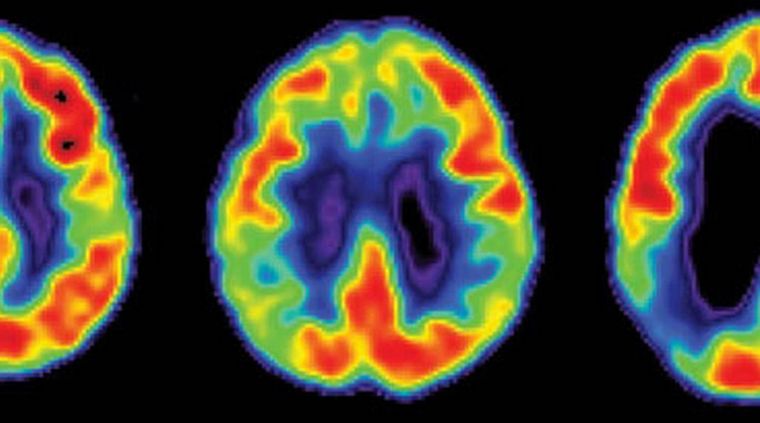

Ir perdiendo progresivamente la memoria es un problema que afecta a millones de personas en todo el mundo. Pero, a diferencia de lo que se cree, no solo la edad y enfermedades neurodegenerativas como el Alzhéimer contribuyen a afectar nuestro cerebro. Ciertas situaciones fisiológicas y algunos hábitos también nos lo ponen más difícil a la hora de almacenar y recuperar recuerdos.

Estrés crónico. Las hormonas del estrés afectan negativamente la función de la corteza prefrontal, una región del cerebro que se ocupa entre otras cosas, de almacenar la memoria de trabajo (que almacena información por un breve lapso de tiempo) y de tomar decisiones. Y todo porque las señales en esta zona se transmiten a través del glutamato, cuyos niveles caen cuando nos estresamos reiteradamente.

Exceso de grasa. Si nuestra dieta incluye demasiadas grasas saturadas y colesterol el cerebro se inflama, la función nerviosa se altera y la memoria de trabajo o memoria inmediata se reduce.

Hipertensión. A partir de los 45 años de edad, la presión arterial alta o hipertensión se asocia con una pérdida de memoria. Los autores lo atribuyen a que la presión sanguínea alta debilita las pequeñas arterias del cerebro, lo que puede desencadenar daños neuronales.